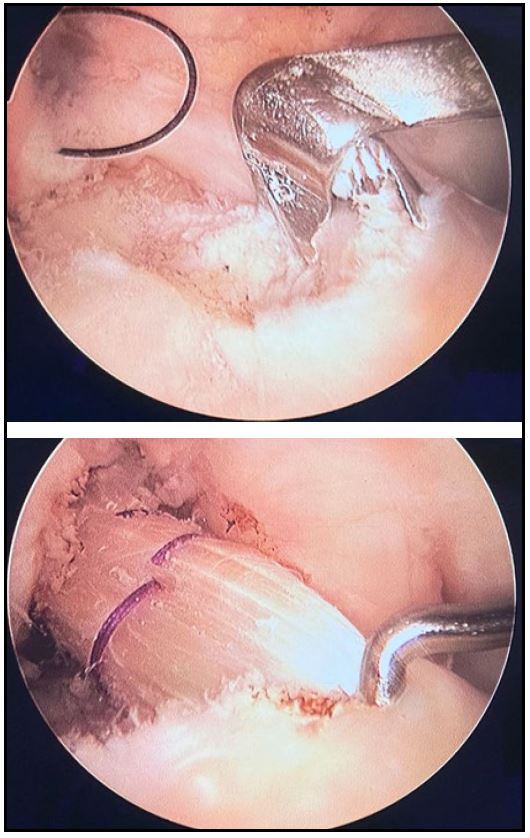

En ambos grupos se utilizó la misma técnica quirúrgica, a través del portal anteromedial para emplazar el túnel femoral, intentando replicar una reconstrucción anatómica (Fig 2). Luego de pasar el injerto a través de los túneles, fueron fijados con 2 tornillos interferenciales con rosca roma; tornillos de titanio, de PEEK o de biocompuesto (según provisión por parte de cobertura social del paciente). Al finalizar la artroscopia, se utilizó la solución fisiológica (con vancomicina, o sin esta) para lavar la incisión de toma de injerto. Cierre de herida por planos.

Figura 2. Colocación y fijación de ST-RI cuádruples según técnica anatómica transportal medial con 2 tornillos interferenciales romos.